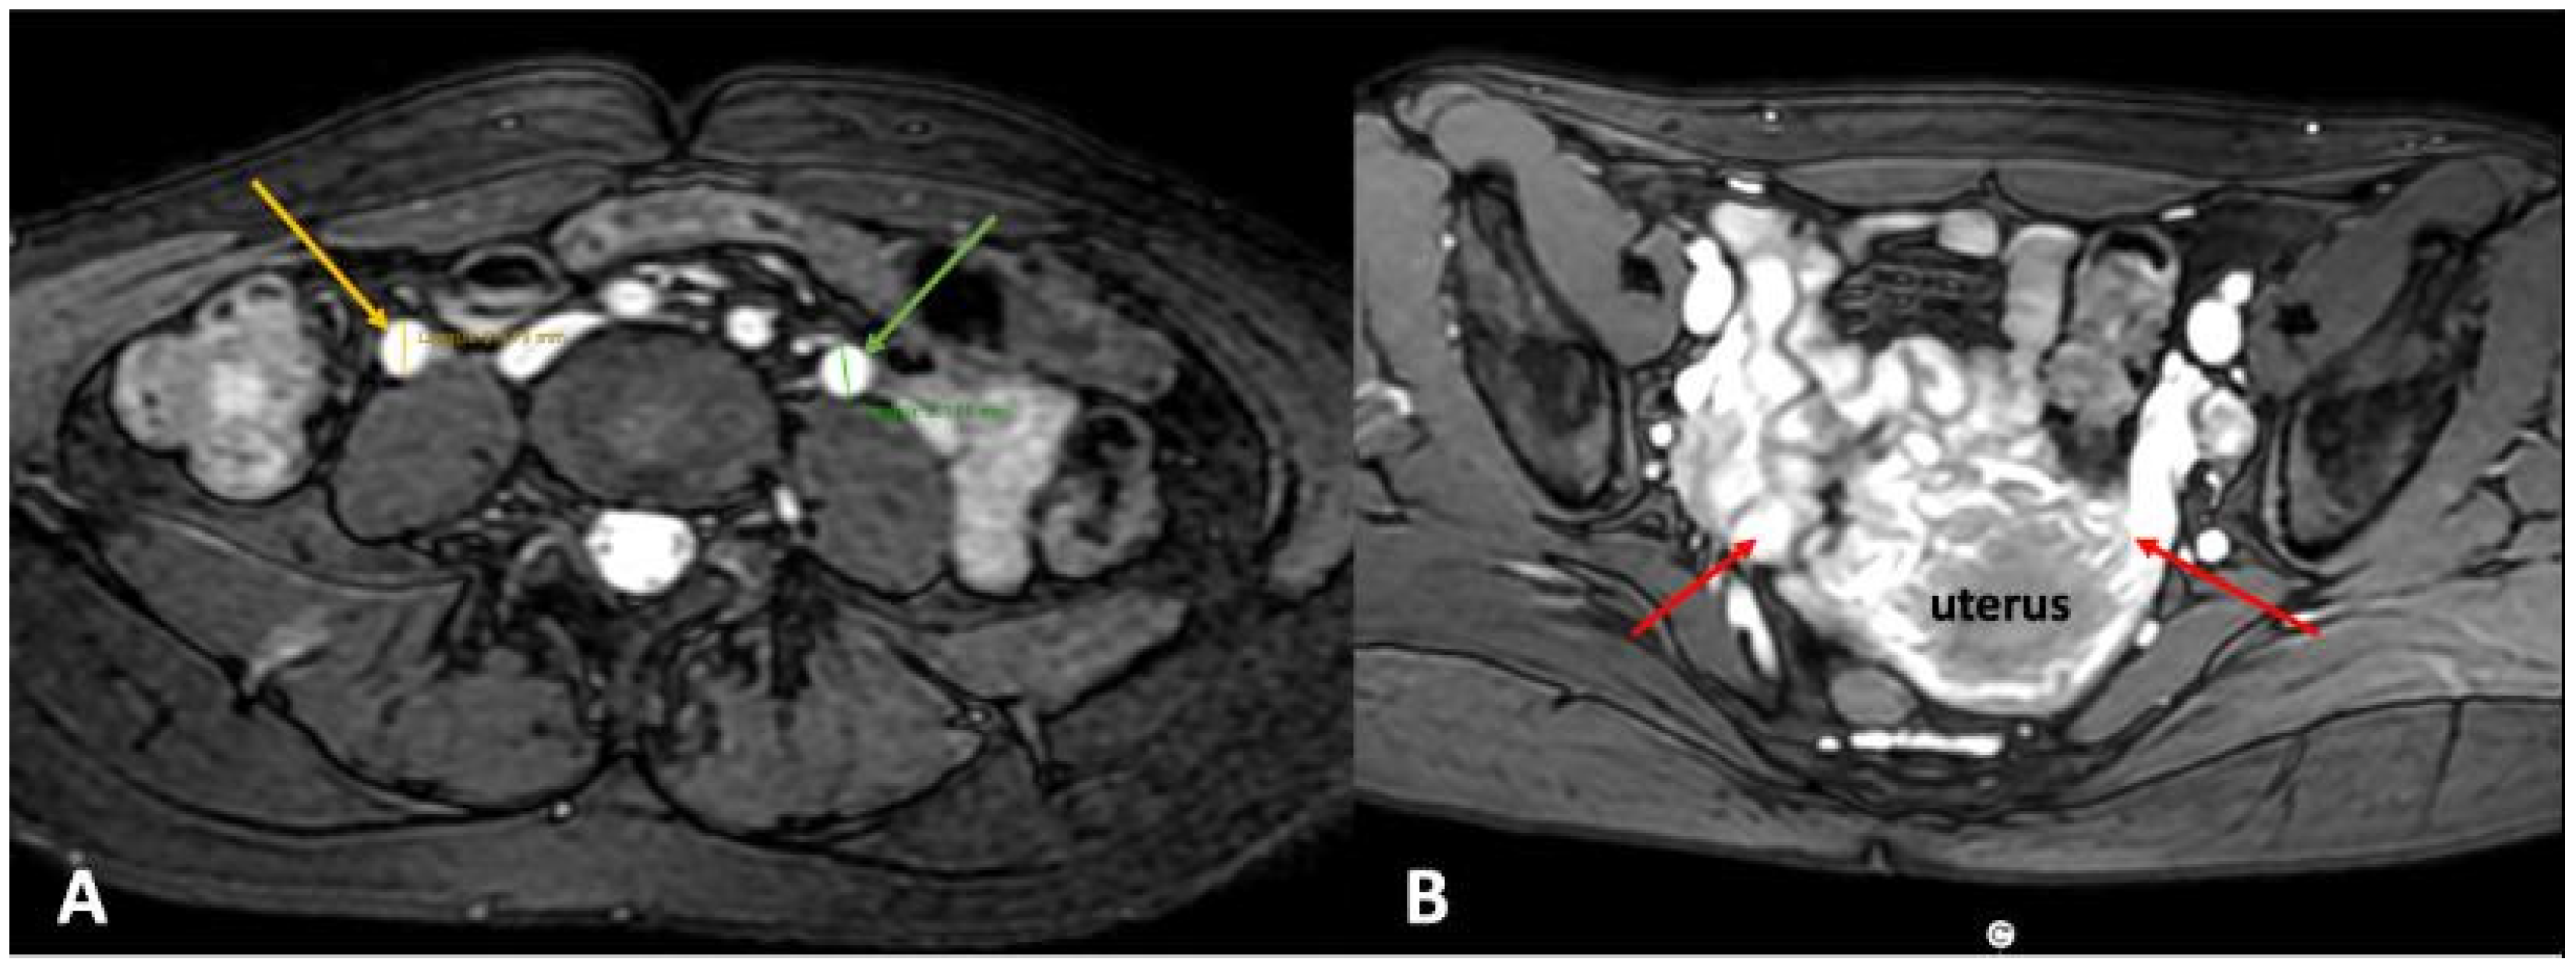

2.3.1. Cross-Sectional Imaging

2.3.2. Catheter Venography and Intravascular Ultrasound